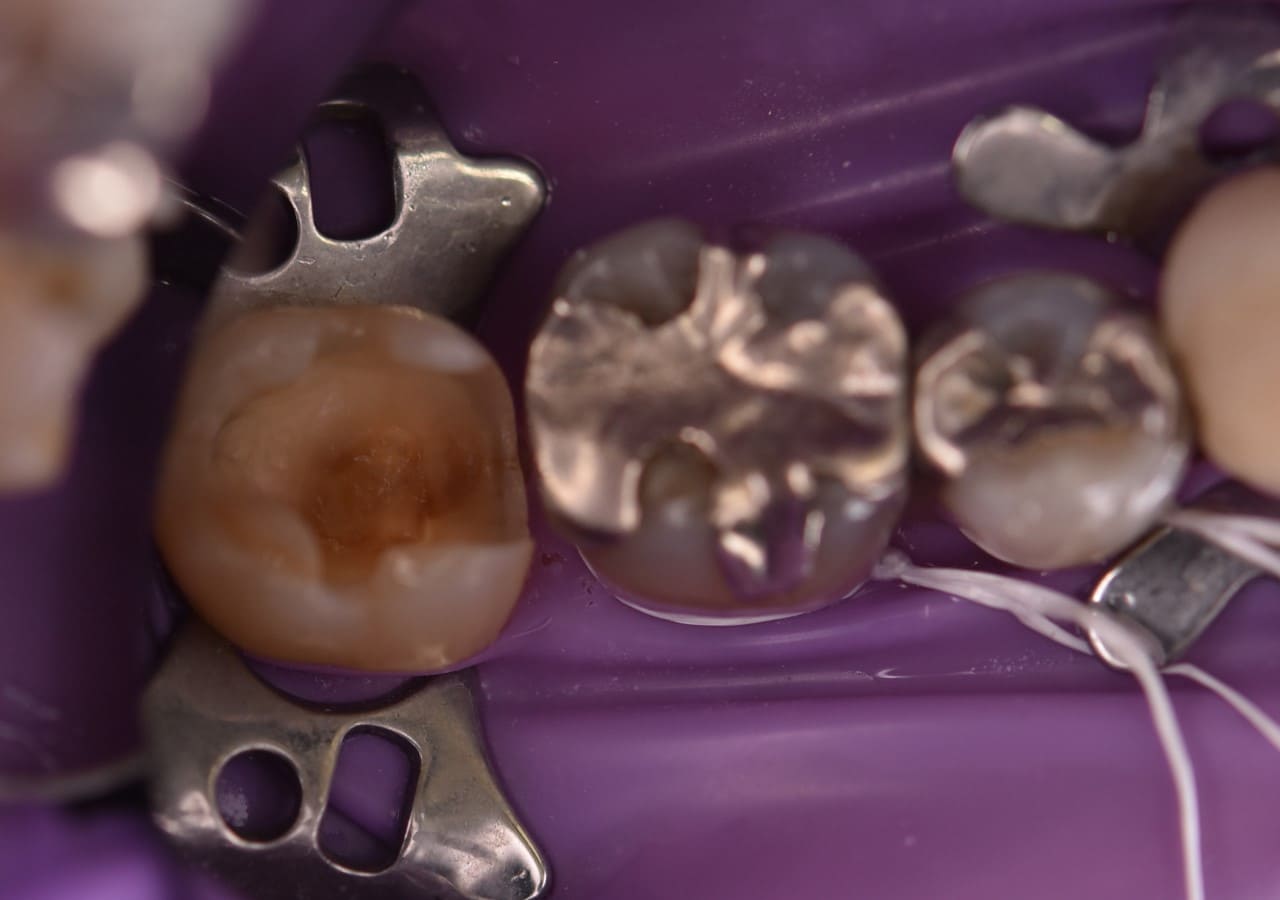

感染防止・治療の質を高めるためにラバーダムを使用します

- 治療部位にラバーダムを装着

歯の周りにゴムシートを設置し、治療する歯に唾液や湿気の感染がないように。そしてお口の中に削った虫歯や銀歯やお水が流れ込まないように、カバーをする装置がラバーダムです。

手順 2

- 銀歯の詰め物を外します

銀歯の下にできた虫歯を除去し、歯の中を形成していきます。

手順 3

- ダイレクトボンディング

ダイレクトボンディングを行い、歯の溝も形成し、自然な歯に近づけます。

手順 4

- 治療完了

ラバーダムを外し治療が完成となります。メタルフリーで身体にも優しい治療なので、おすすめいたします。

当院はダイレクトボンディング治療では、ほとんどのケースでラバーダムを使用しています。